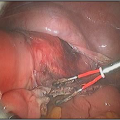

How are Hysteroscopic operations performed ?

The hysteroscope allows good vision inside the uterus .The uterus is kept distended by a continuous flow of a liquid by� specialised pressure-controllong device. Specialised fine electrosurgical tools are passed into the cavity under vision and the pathology is tackled. The patient goes home the same day.